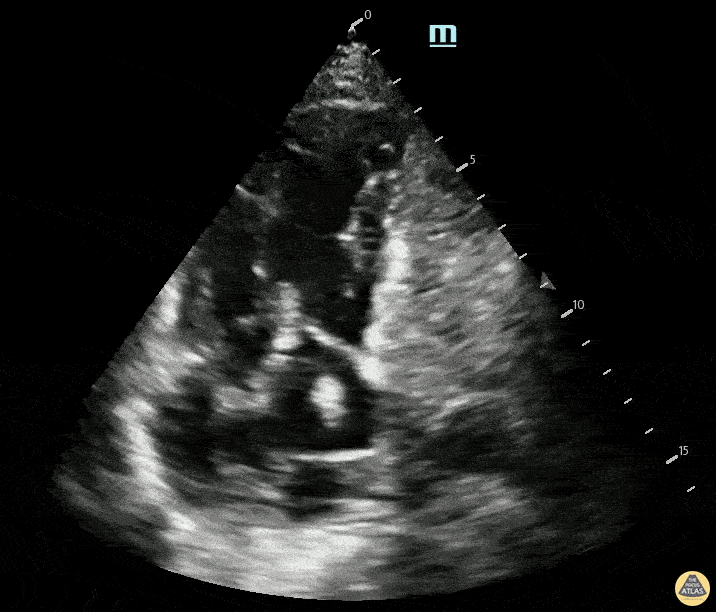

A 29-year-old with a recent mild COVID-19 infection presents with 5 days of fever, abdominal pain, myalgias, and arthralgias. On arrival, the patient is hypotensive at 80/50 mmHg with HR 100 bpm. There is concern for post-viral myocardial involvement. POCUS shows the following. Please describe the findings seen in this scan.

Findings: RV- low tapse, LV- FS<30%, poor squeezed

What is biventricular failure secondary to post-COVID myocarditis?